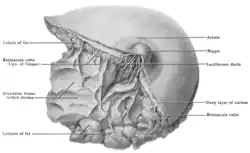

Dissection of human breast: Cooper's ligaments labeled as "Retinacula cutis (Ligs. of Cooper)" and "Retinacula cutis" | |

Cooper's ligaments (also known as the suspensory ligaments of Cooper and the fibrocollagenous septa) are connective tissue in the breast that help maintain structural integrity. They are named for Astley Cooper, who first described them in 1840.[1][2] Their anatomy can be revealed using Transmission diffraction tomography.[3]

The ligaments run from the clavicle and the clavipectoral fascia, branching out through and around breast tissue to the dermis of the skin overlying the breast. The intact ligament suspends the breast from the clavicle and the underlying deep fascia of the upper chest. This has the effect of supporting the breast in its normal position, and maintaining its normal shape. Without the internal support of this ligament, the breast tissue (which is heavier than the surrounding fat) sags under its own weight, losing its normal shape and contour.